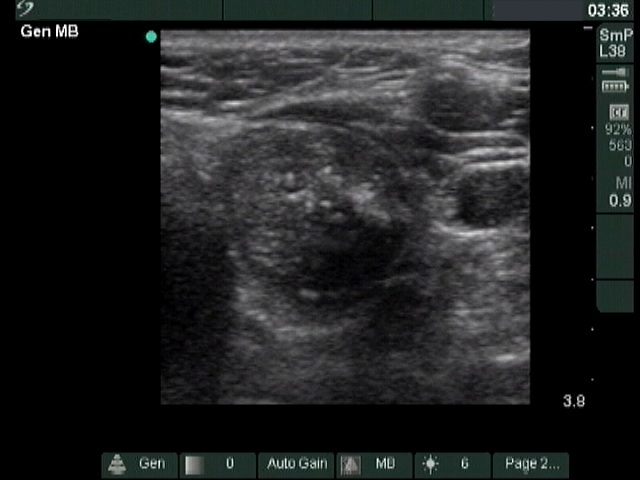

The composition of the nodule - case 1033 (ultrasonographic picture 4)

Middle-lower part of the left lobe, transverse scan. There is a cystic area dorsal to the solid part. In this section the lesion seems to be a peripheral-type cyst.